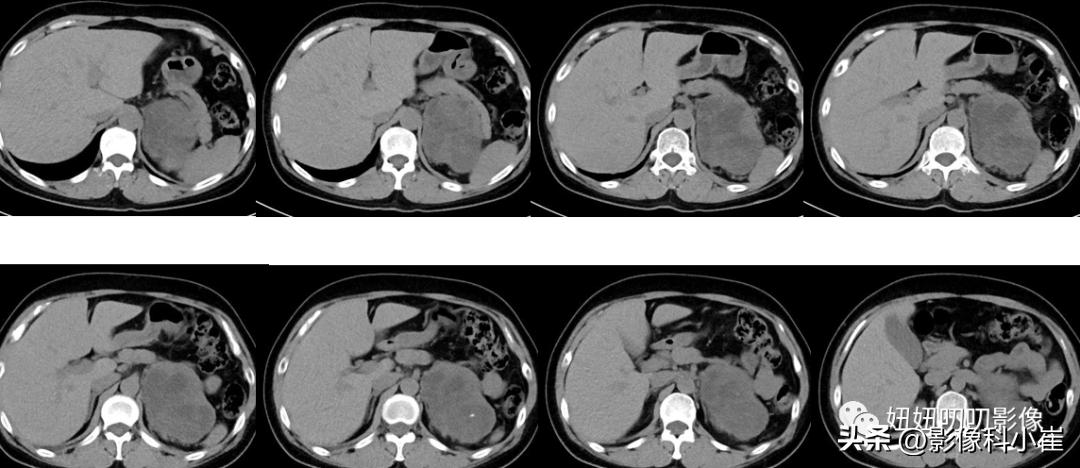

病史:

女,57岁,主诉:查体发现左肾上腺占位10天。最近测血压最高150/85mmHg。

影像描述:

左侧肾上腺区见一团块状等长T1 等长T2 混杂信号,边界尚清,DWI示部分弥散受限,T1 反相位信号未见明显减低,最大截面约9.7X7.0X71,其内见点状短T2 信号,增强扫描呈明显渐进性不均匀强化,邻近组织受压。右侧肾上腺形态、信号未见异常,增强后未见异常强化。双肾见小圆形长T1长T2 信号,边界尚清,增强扫描未见明显异常强化。腹腔及腹膜后未见明显增大淋巴结。腹腔内未见明显液体信号灶。